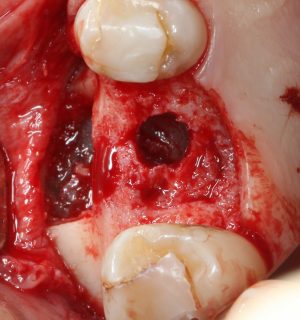

Клинический случай — двадцать шестой зуб, установка имплантата Astra Tech и синуслифтинг.

Сосредоточимся на установке имплантата Astra Tech Osseospeed TX, ибо синуслифтинг мы обсуждали ранее, здесь, здесь, здесь, тут и еще здесь. На данном примере я покажу вам установку имплантата Astra Tech Osseospeed TX 5.0х9 мм.

Изначальная клиническая ситуация

Пациенту удалили 26 зуб около двух месяцев назад. Вот компьютерная томография

Подробнее:

В общем, тут нужен синуслифтинг. И, исходя из последних данных об этой операции, 2,6 мм до дна верхнечелюстной полости достаточно, чтобы нормально стабилизировать имплантат, в т. ч. Astra Tech.

26 зуб удалён относительно недавно, поэтому альвеолярный гребень сохранил ширину — это даст нам возможность поставить бескомпромиссно большой по диаметру имплантат — 5.0 мм.

В этой конкретной клинической ситуации первичная стабильность не зависит от длины имплантата, поэтому длину можно выбирать любую. Мы возьмём оптимальную — 9.0 мм. Ибо проще будет с синуслифтингом.

Начинаем подготовку лунки под имплантат